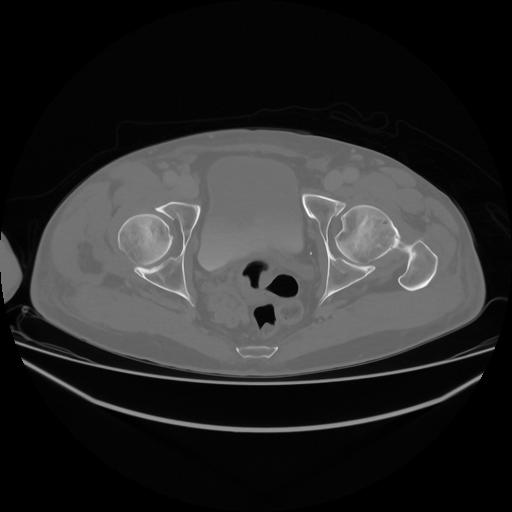

5 CUERPO,CE,Vol,1.0,CUERPO,,